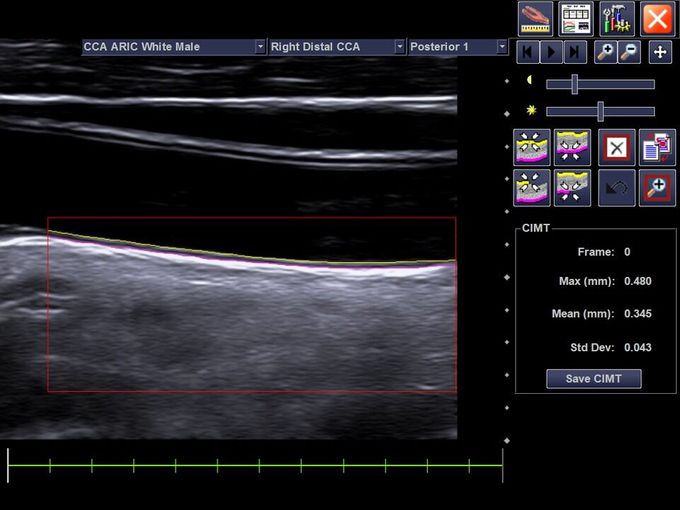

Кроме новой техники, можно заказать восстановленные медицинские системы: ультразвуковые сканеры, томографы, флюороскопы, ангиографы и хирургические установки С-дуга.